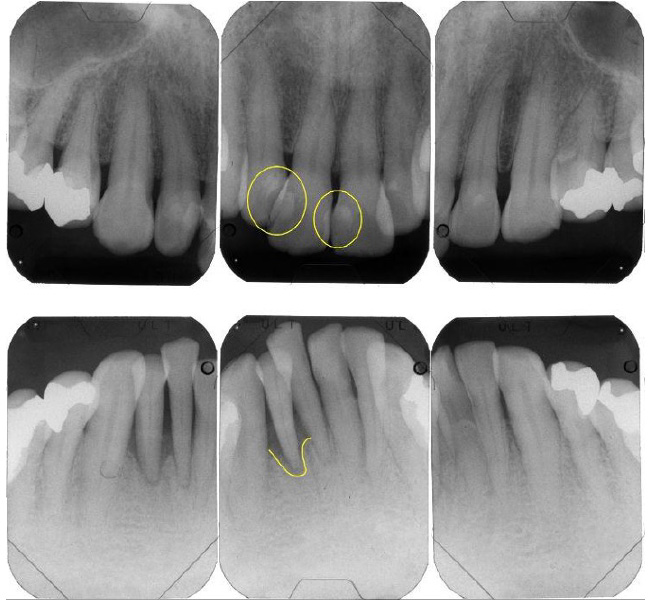

治療前

| 治療内容 | 全顎治療:歯周病治療、抜歯、根管治療、 咬合治療・矯正治療、フルメタルクラウン(保険) |